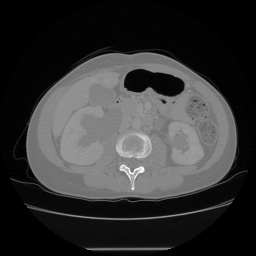

由于医学影像的独特属性,在大多数情况下其详细数据不会被广泛分享。现将一个公开获取的数据库——3D-IRCADB介绍如下:该数据库包含来自20名患者的CT扫描图像序列;具体而言,每个患者大约拥有几百张左右的扫描图像。这些扫描通常以 DICOM 格式存储;此外,在进行深度学习分析时,默认也会使用对应的掩膜(mask),这些掩膜同样采用 DICOM 格式存储。为了便于后续处理和分析,在此将原始 DICOM 格式的图像转换为 PNG 格式保存;长图:image:

label: